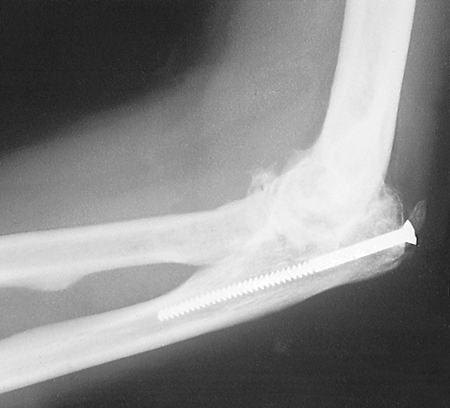

comminuted fracture of the left olecranon process in a motor vehicle

accident and was treated elsewhere with screw fixation of the olecranon

and long-arm cast immobilization for 1 month. He presented 6 months

later with ankylosis of the left elbow at 75 degrees of flexion with

the radiograph showing

marked narrowing of the elbow joint (Fig. 22-24). Cutis arthroplasty was performed with a lower abdominal donor site (Fig. 22-25).

![]() |

Figure 22-24. Posttraumatic arthrosis in a 43-year-old right-handed electrician.